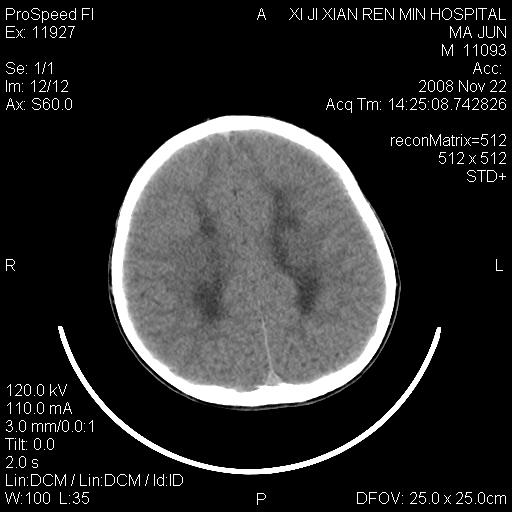

标题: PED1650:男 8岁 间断抽搐2年 两岁是在外院诊断脑瘫 当时CT示 [打印本页]

标题: PED1650:男 8岁 间断抽搐2年 两岁是在外院诊断脑瘫 当时CT示

双侧侧脑室前角,三角区旁及半卵圆中心区白质呈低密度改变,半卵圆中心区病灶呈片状融合趋势,无软化征像,脑室无扩张,各神经核团无异常改变,脑皮质无萎缩等征像,结合病史考虑髓鞘发育不良性脑白质病,异染性脑白质营养不良可能性大.不除外多发性硬化等其他改变,建议磁共振检查

脑白质减少,双侧侧脑室额角旁及半卵圆中心可见对称性略低密度影,边缘尚清,考虑脑白质发育不良